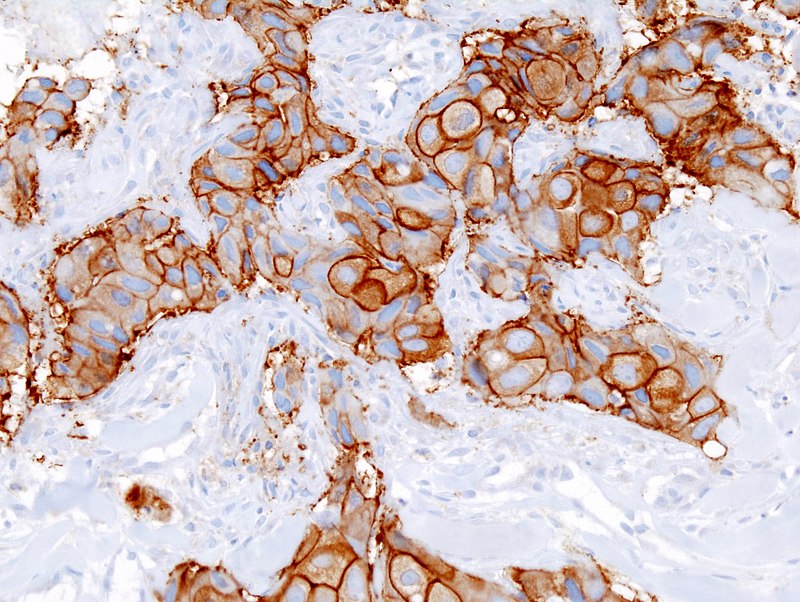

- HER2/neu gene amplification (overexpression) status

Response to trastuzumab (aka Herceptin), a synthetic antibody targeting the HER2 receptor, is linked to HER2/neu amplification.

On the cell surface, there is a growth factor receptor called HER2/neu.